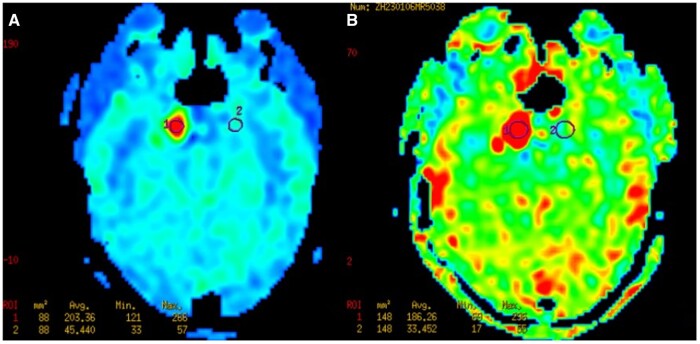

Generally, due to the complexity of the skull base structures, it is difficult to differentiate cavernous vascular malformation and meningioma in the cavernous sinus area using conventional imaging studies. Cavernous sinus venous malformation are characterized by increased capillary masses without a direct arterial supply, typically leading to low perfusion. On the other hand, meningiomas receive arterial blood supply to the tumour and often exhibit high perfusion. So, arterial spin labelling (ASL) can be helpful in distinguishing between the 2 tumour types. However, in our specific case of a cavernous sinus venous malformation, the ASL imaging showed hyperperfusion. Further analysis revealed that this hyperperfusion on ASL can occur when cavernous sinus venous malformation is associated with arteriovenous fistula malformation.